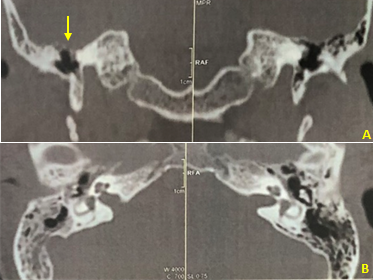

Figure 6 Postoperative Computed tomography of temporal bone.

Coronal section. B. Axial section. There is an absence of tympanic tegmen bone defects and a good aeration of the middle ear and mastoid cells.